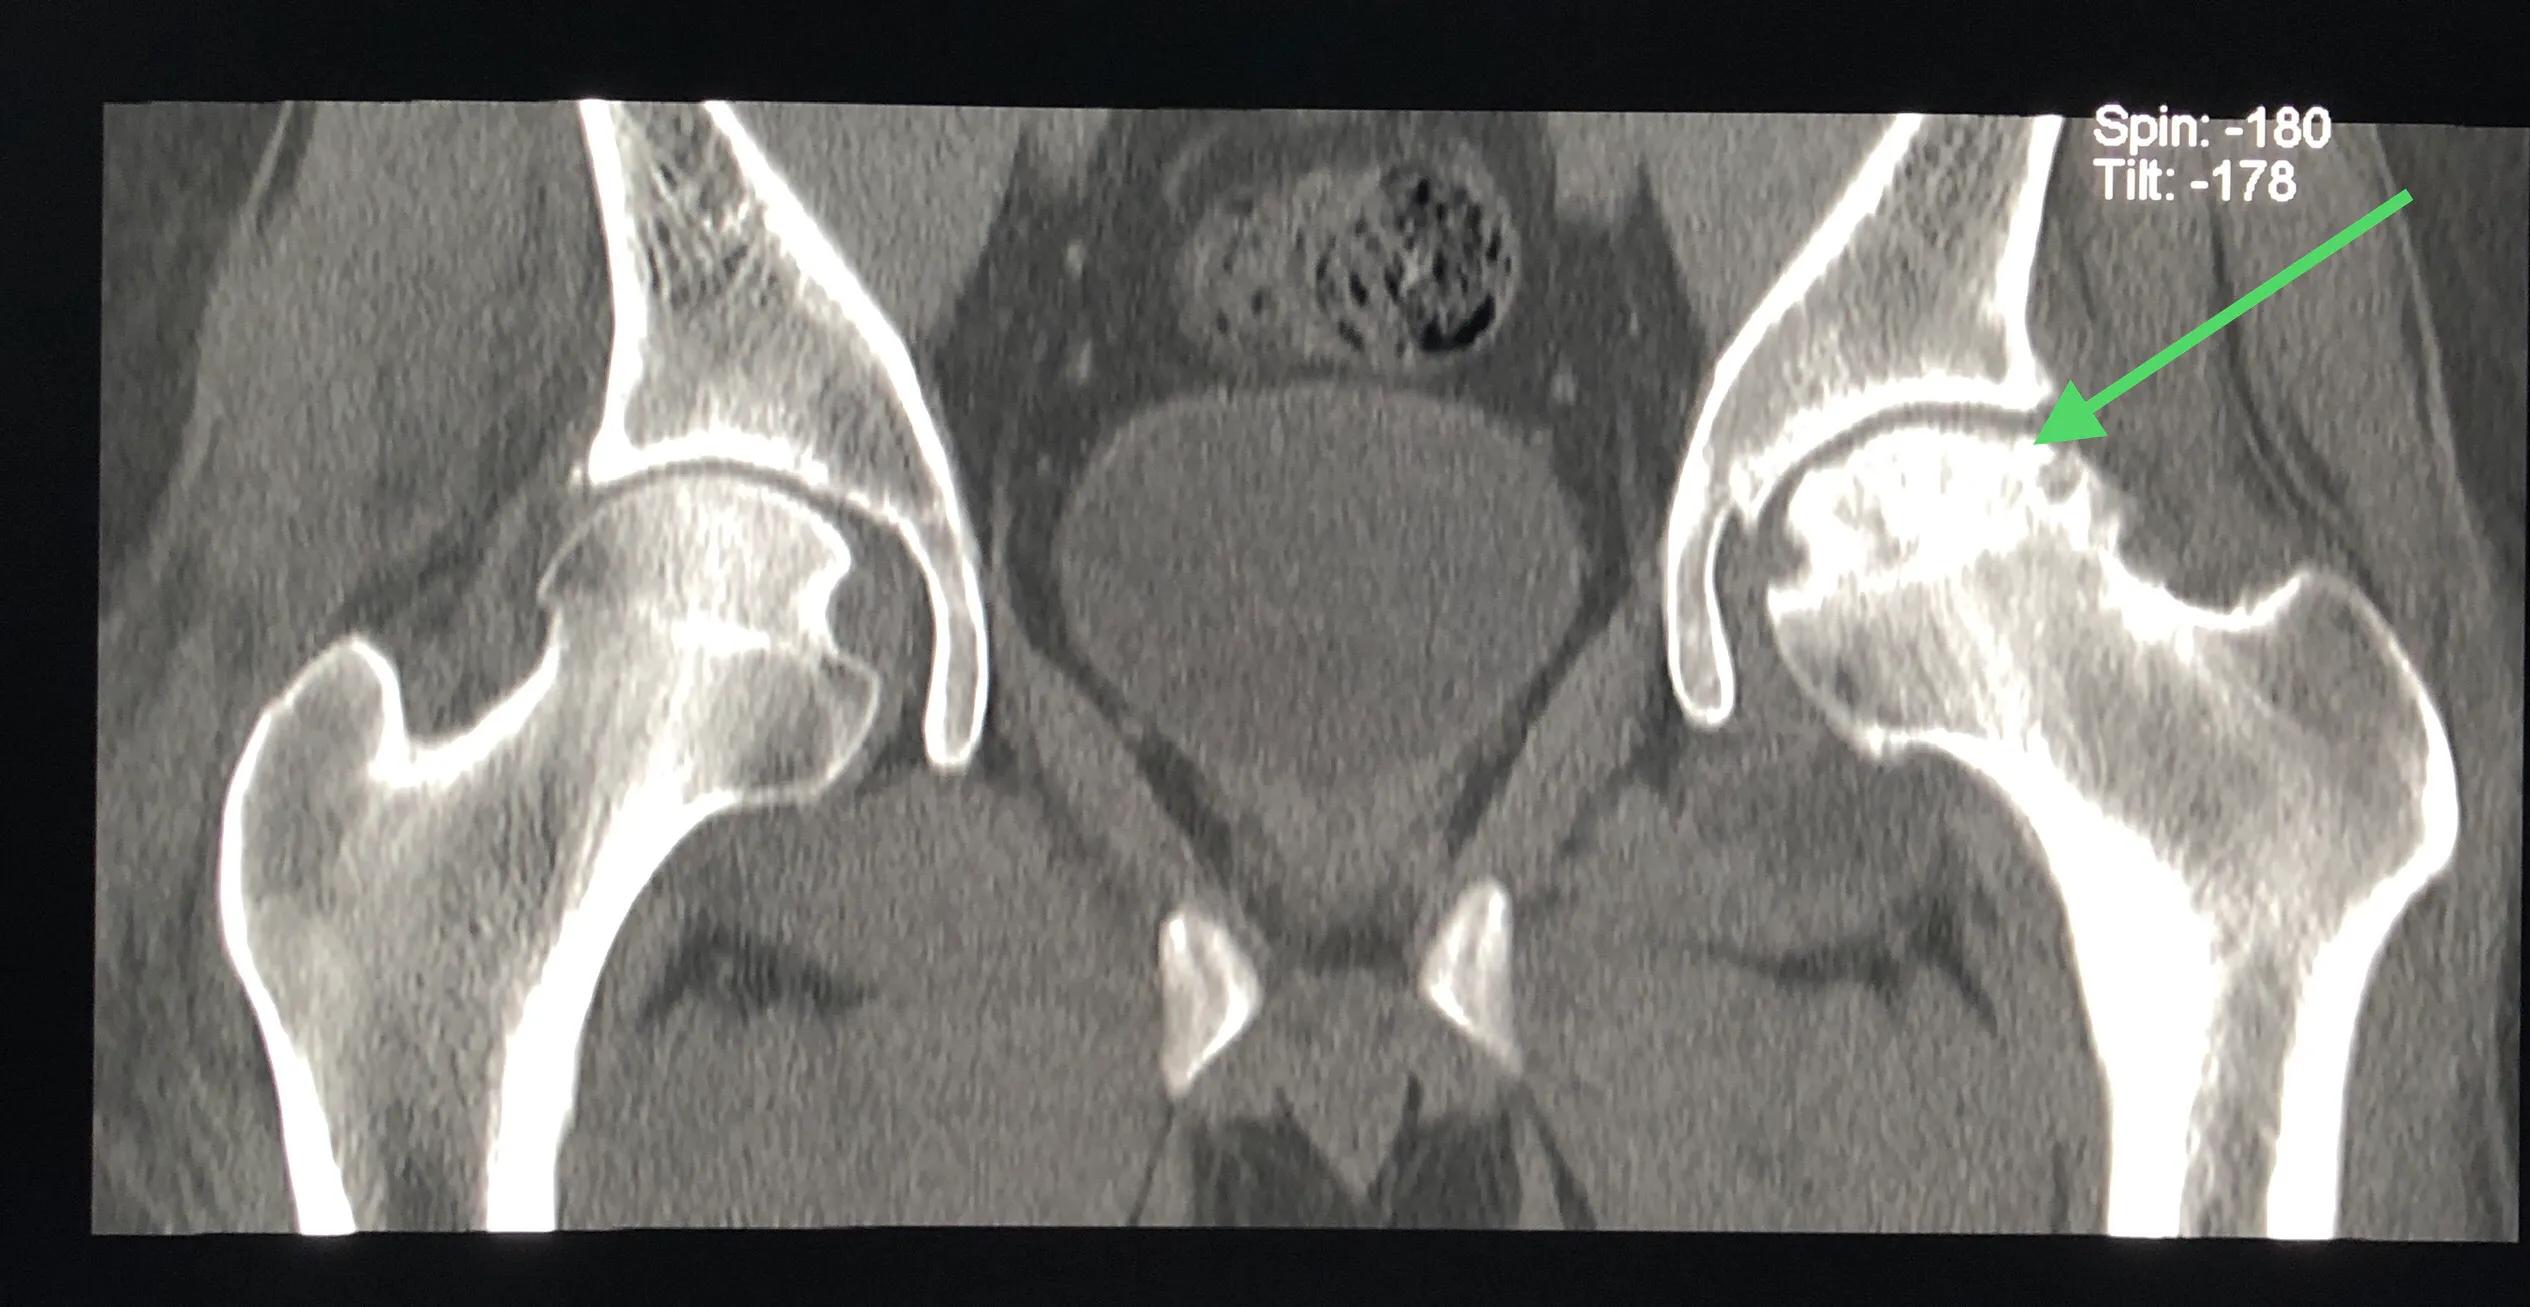

图12: CT。左侧股骨头坏死4期。

图13: CT。左侧4期 股骨头基本坏死吸收殆尽(圆圈示)。对比右侧容易理解。